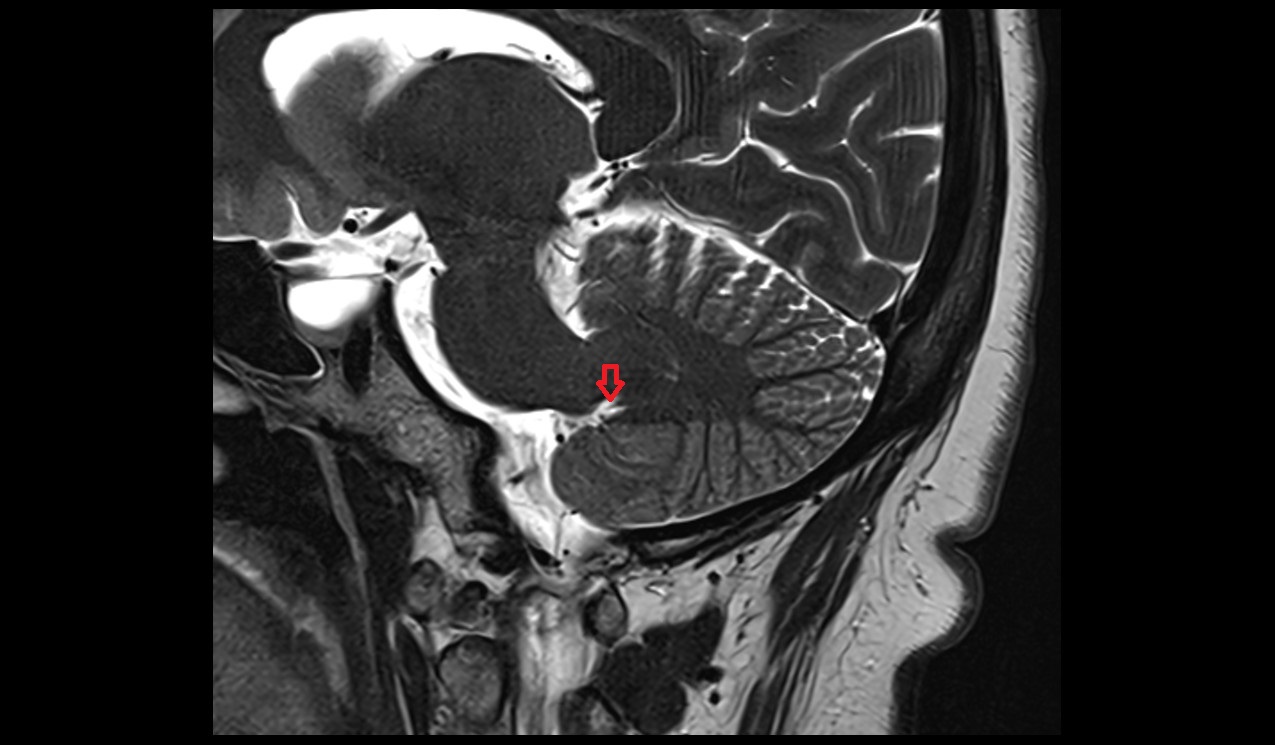

- Median aperture of fourth ventricle (foramen of Magendie)